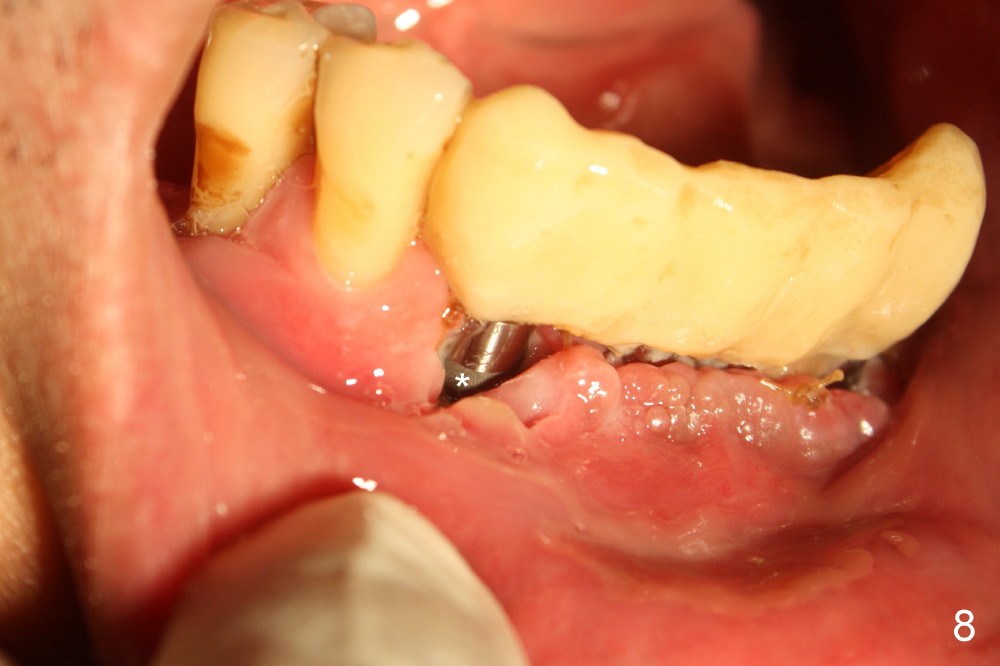

The wound is gapping over the implants (Fig.8), while #20 and 21 sockets are healing one week postop (Fig.9).